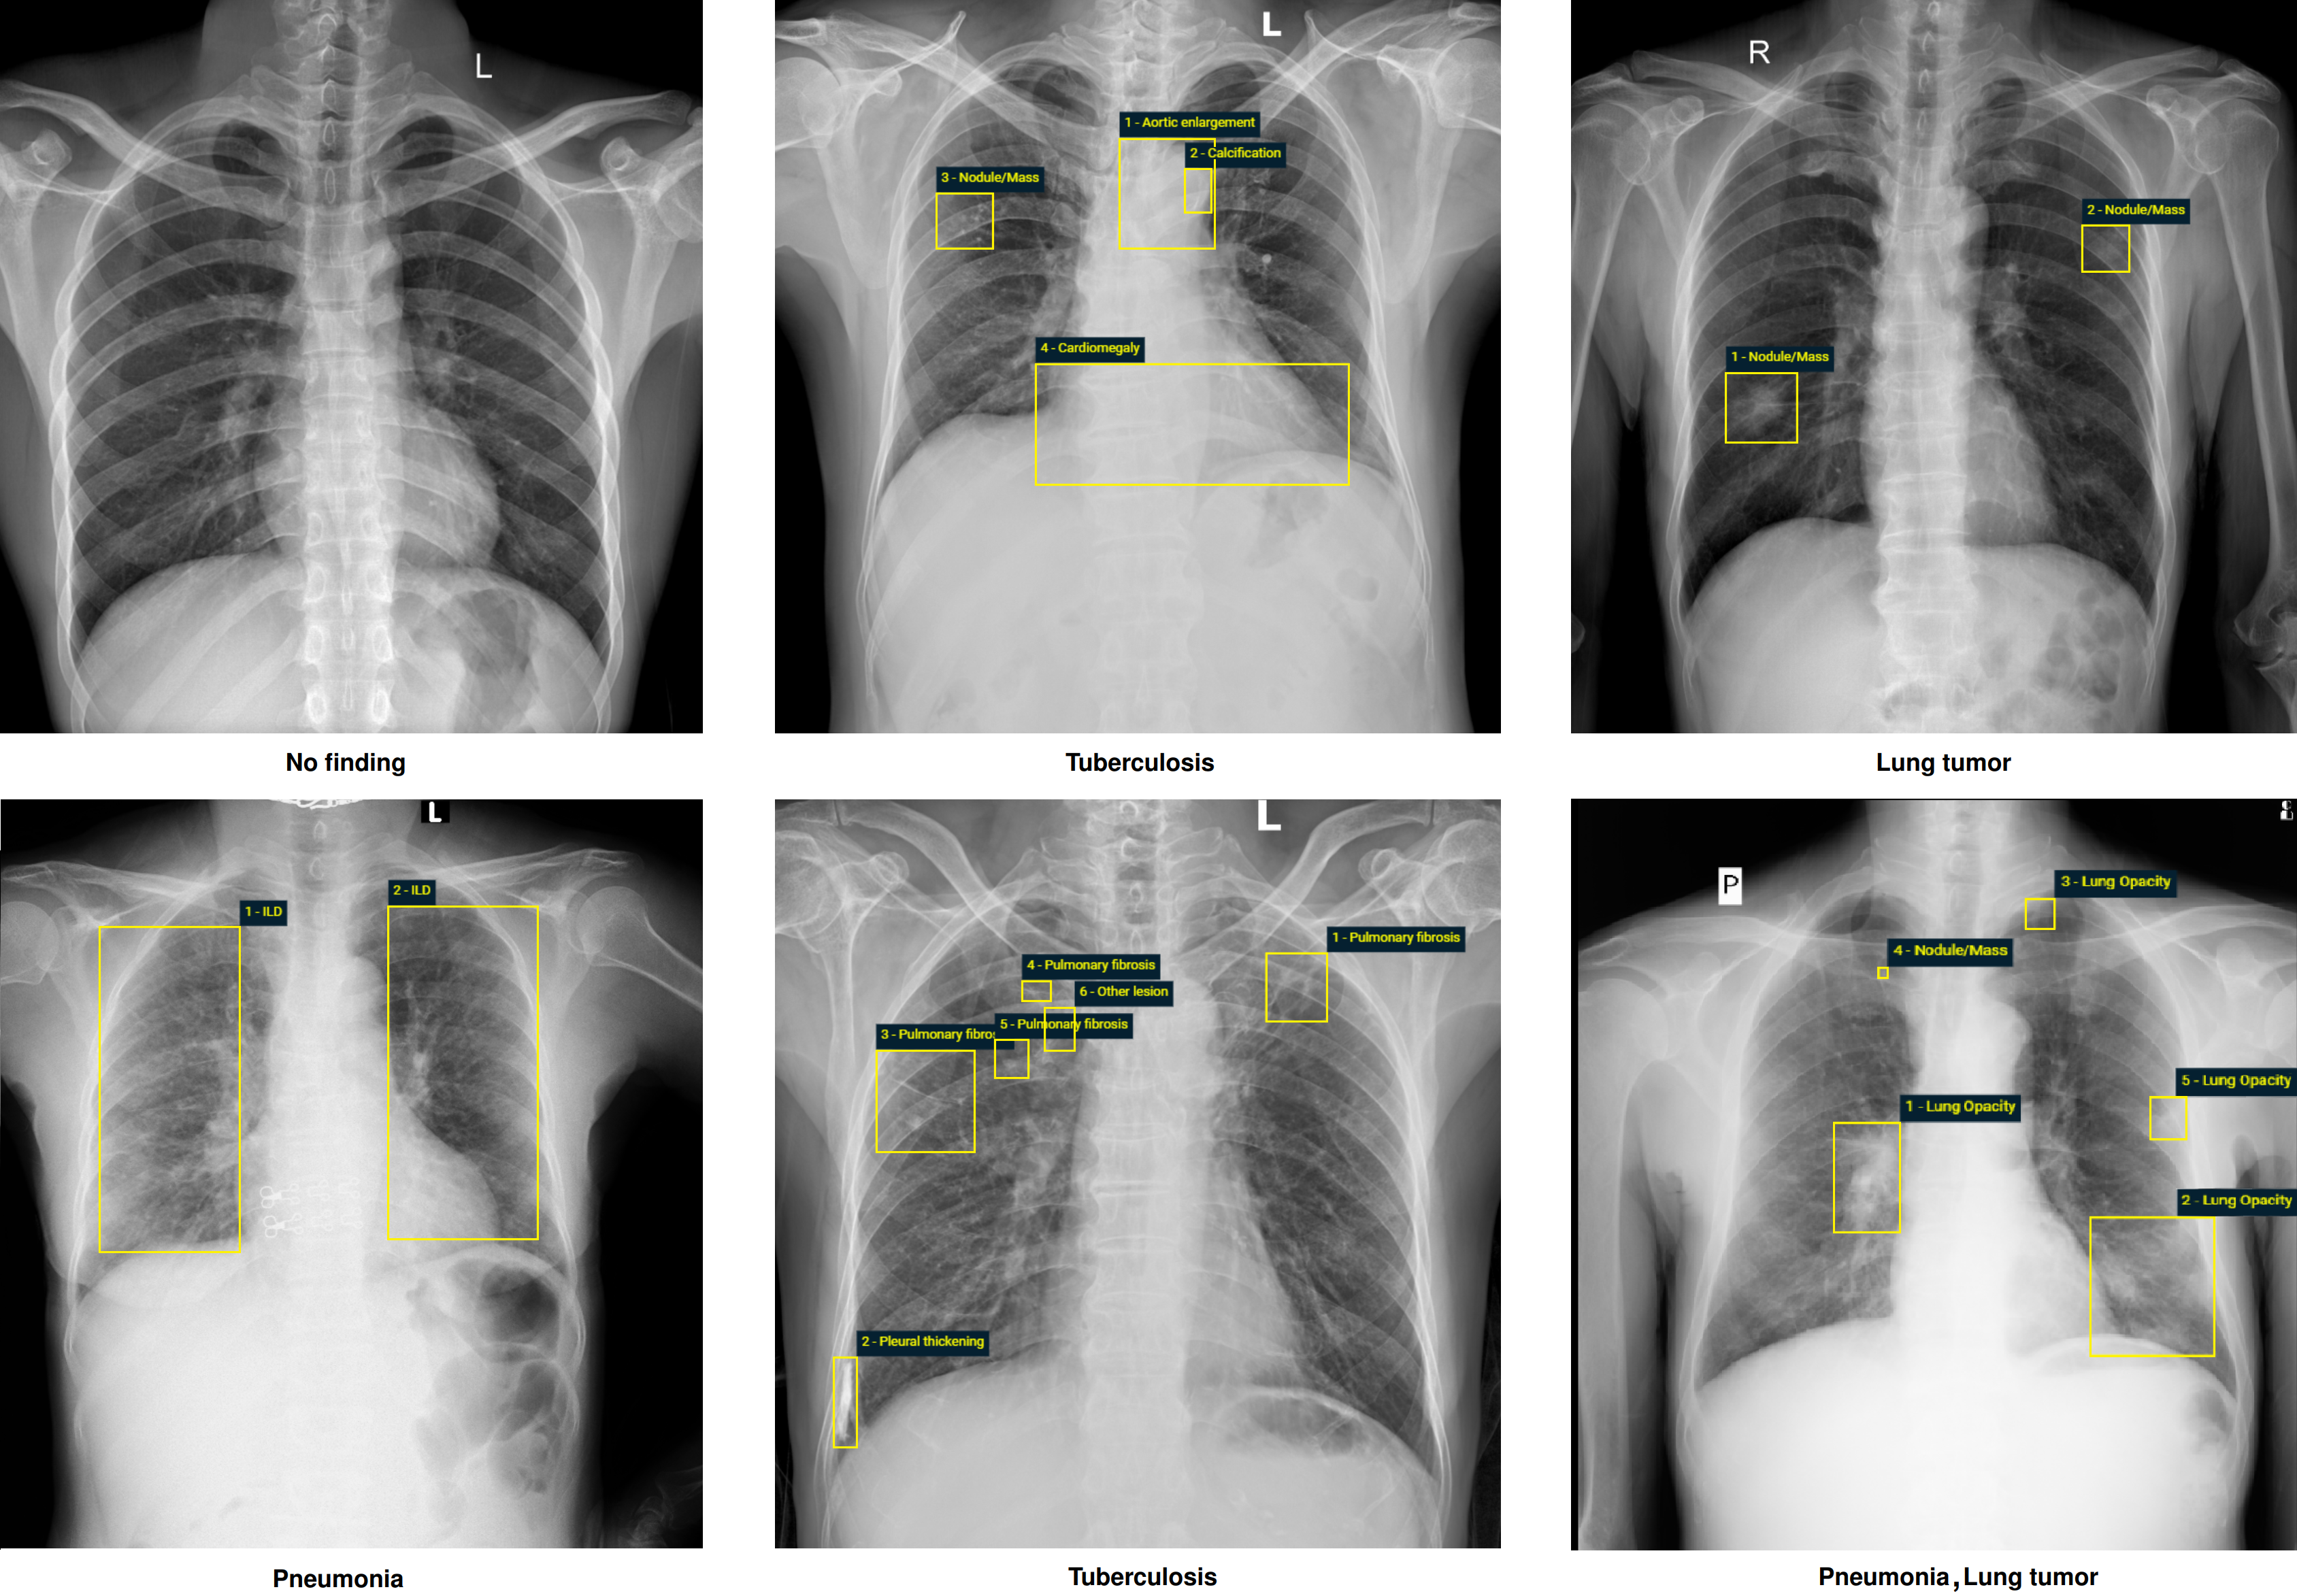

The dataset contains more than 100,000 chest X-ray scans that were retrospectively collected from two major hospitals in Vietnam. Out of this raw data, we released 18,000 images that were manually annotated by a total of 17 experienced radiologists with 22 local labels of rectangles surrounding abnormalities and 6 global labels of suspected diseases. The released dataset is divided into a training set of 15,000 and a test set of 3,000. Each scan in the training set was independently labeled by 3 radiologists, while each scan in the test set was labeled by the consensus of 5 radiologists. All images are in DICOM format and the labels from training and test sets are made publicly available.

Examples of CXRs with radiologist’s annotations. Abnormal findings (local labels) marked by radiologists are plotted on the original images for visualization purposes. The global labels are in bold and listed at the bottom of each example.